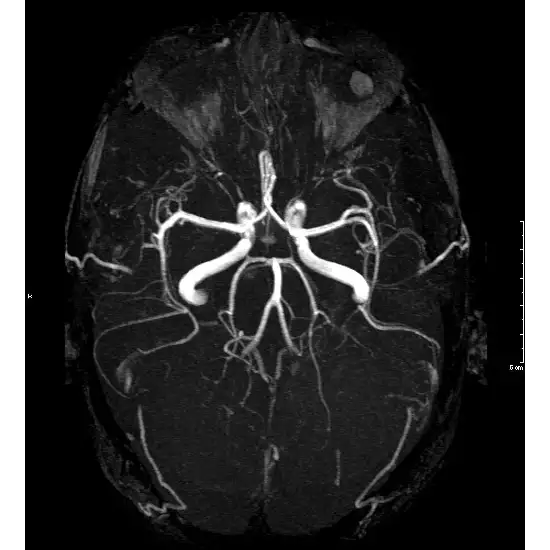

The MR Angiography Brain With Contrast is a non-invasive scan which is used to get pictures of blood vessels in the brain. MRA Brain helps in detecting the blood flow in arteries, aneurysm, blockages or any abnormalities in blood vessels. A contrast dye is used during the procedure as it helps in detecting the images more clearly.

MRA (Magnetic Resonance Angiography) with contrast of the brain is done to study the blood vessels in the brain to check if there is a bulge (aneurysm), a clot, or a narrowing (stenosis) because of plaque. Indications of MR Angiography of brain with contrast are-